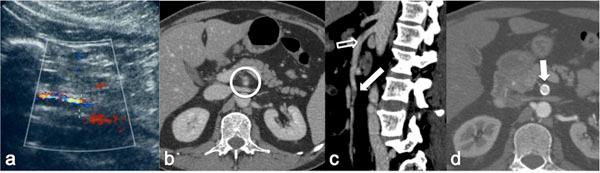

Acute vascular emergencies can arise from direct traumatic injury to the vessel or be spontaneous (non-traumatic).The vascular injuries can also be divided into two categories: arteial injury and venous injury.Most of them are life-treatening emergencies, sice they may cause an important ipovolemic shock or severe ischemia in their end organ and require prompt diagnosis and treatment.In the different clinical scenarios, the correct diagnostic approach to vascular injuries isn't firmly established and advantages of one imaging technique over the other are not obvious.Ultrasound (US) is an easy accessible, safe and non-invasive diagnostic modality but Computed Tomography (CT) with multiphasic imaging study is an accurate modality to evaluate the abdominal vascular injuries therefore can be considered the primary imaging modality in vascular emergencies.The aim of this review article is to illustrate the different imaging options for the diagnosis of abdominal vascular emergencies, including traumatic and non traumatic vessel injuries, focusing of US and CT modalities.

急性血管急症可由血管直接外伤引起,也可为自发性(非外伤性)。血管损伤也可分为两类:动脉损伤和静脉损伤。它们大多是危及生命的急症,因为它们可能导致重要的低血容量性休克或其终末器官的严重缺血,需要及时诊断和治疗。在不同的临床情况下,针对血管损伤的正确诊断方法尚未完全确立,一种成像技术相对于另一种成像技术的优势并不明显。超声(US)是一种易于获得、安全且无创的诊断方式,但多期成像研究的计算机断层扫描(CT)是评估腹部血管损伤的准确方式,因此可被视为血管急症的主要成像方式。本文综述的目的是阐述用于诊断腹部血管急症的不同成像选择,包括外伤性和非外伤性血管损伤,重点介绍超声和CT方式。